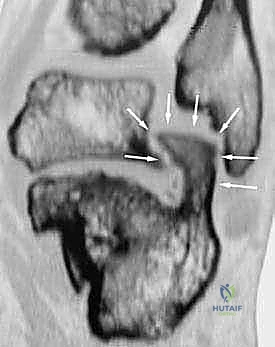

- الأشعة المقطعية ثلاثية الأبعاد (3D CT Scan): وهي الخطوة الذهبية والأهم في عيادة الدكتور هطيف. تتيح هذه الأشعة بناء نموذج ثلاثي الأبعاد دقيق للكعب المشوه، مما يسمح بتحديد أماكن الانحشار العظمي بدقة المليمتر، ومعرفة مدى تلف الأسطح المفصلية. بناءً على هذه الصور، يتم وضع خطة "القطع العظمي التصحيحي" قبل دخول غرفة العمليات.

- القطع العظمي التصحيحي (Corrective Osteotomy):

إذا كان الكعب قد فقد ارتفاعه أو انحرف بشكل كبير، يقوم الدكتور هطيف بإجراء قطع دقيق في عظم الكعب لإعادة توجيهه إلى محوره الميكانيكي السليم. يتم استخدام طعوم عظمية (Bone Grafts)—تؤخذ غالباً من حوض المريض أو طعوم صناعية—لرفع الكعب المنهار واستعادة زاوية بوهلر الطبيعية.